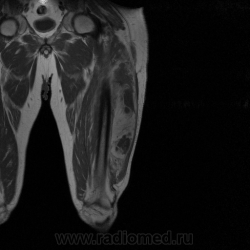

Ну вот аксиальные срезы, где то затерял =(

С учетом вашего опыта, мне кажется Вам и без дословной интерпретации МР-протокола будет все понятно.

Мой коллега в заключении указал о вероятней всего рабдолейомиосаркоме, если я ошибся то чуть позже поправлюсь.

Я тоже пока что в этом деле лось, но думаю дело поправимое, на днях улетаю С-Петербуг в МАПО(цикл КТ и МРТ), ну да ладно, что косается пациента то он ещё в 2007 году обращался по месту жительства к травматологу по поводу ушиба бедра с формированием гематомы, была назначена местная рассасывающая терапия, до 2009г. видимо ждали пока рассасется в декабре обратился к хирургу по поводу посинения и увеличения в объёме задней поверхности бедра, назначен гепарин в феврале был вскрыт абсцесс в этом месте, далее только в марте сподхватились по УЗИ-мягких тканей признаки образования, ну и открытая ножевая биопсия: Описание изменений, выявленных при микроскопическом исследовании: в материале фрагменты опухоли, представленной пучками вытянутых клеток с полиморфными гиперхромными, местами уродливыми ядрами. Определяется значительное количество митозов, встречаются поля некроза опухоли. При иммуногистохимическом исследовании опухолевые клетки экспрессируют виментин, отсутствует реакция на десмин, гладко-мышечный актин, S100. Патоморфологическое заключение: саркома мягких тканей, боее вероятно фибросаркома.